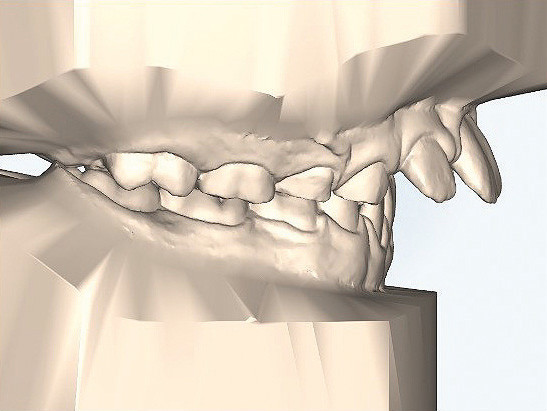

Klinisches Fallbeispiel 2 (Abb. 2a–y)

Distalbiss und tiefer Biss bei einem zwölfjährigen Mädchen. Die Behandlung erfolgte mit Invisalign und Precision Wings. Insgesamt waren zwei Schienensätze notwendig. Die Gesamtbehandlung dauerte 18 Monate.Bei der Planung des ClinCheck wurde der tiefe Biss vorwiegend über eine Intrusion der Unterkieferfront behoben, um die Lachlinie der Patientin nicht negativ zu beeinflussen. Die Oberkieferfront wurde nur retrudiert, jedoch vertikal nicht intrudiert. Während der Phase des Mandibular Advancement wurde die Wirkung der Precision Wings durch den Einsatz von Klasse II-Gummizügen unterstützt. Schlussendlich wurde auch der hängenden Okklusionsebene durch eine einseitige Intrusion der Molaren im ersten Quadranten Rechnung getragen.